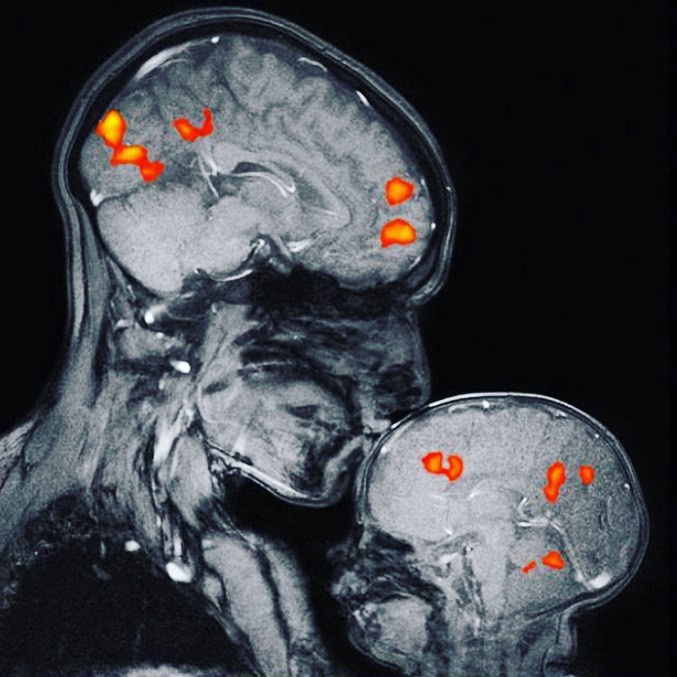

"Toto je vôbec prvý magnetický rezonančný obrázok na svete, ktorý zobrazuje puto matky a dieťaťa.

Na obrázku je neurovedkyňa Rebecca Saxe bozkávajúca svojho dvojmesačného syna.

Mozog dieťaťa sa zdá byť hladší a tmavší. Je to preto, že má výrazne menej bielej hmoty. Biela hmota sa skladá z myelínu, čo je tukové tkanivo, ktoré pôsobí ako izolácia drôtov, ktoré komunikujú správy vo vašom mozgu.